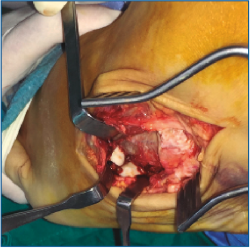

Es intervenido a la semana de la lesión realizándose, bajo anestesia raquídea e isquemia del miembro, una incisión dorsolateral desde la articulación calcaneocuboidea hasta la base del 4.º MTT. Se expuso el cuboides reflejando el extensor corto a dorsal y peroneo corto a plantar y se evidenció la desalineación del cuboides con el 4.º y 5.º MTT y el calcáneo creada por la luxación. Se realizó una reducción manual del mismo y una fijación con 2 agujas de Kirschner (agujas K) metatarsocuboideas, 1 aguja cuboideocalcánea y 1 calcaneocuboidea, realizándose al mismo tiempo una fijación de la apófisis lateral del astrágalo con un tornillo canulado (Figuras 3, 4 y 5). Se mantuvo 6 semanas inmovilizado, momento en el que se retiraron las agujas K. A la 6.ª semana, se inicia la carga con ortesis de carga hasta la 8.ª semana.

Figura 5. Imagen intraoperatoria de la reducción del cuboides y fijación con 2 agujas de Kirschner metatarsocuboideas, 1 aguja cuboideocalcanea y 1 calcaneocuboidea.